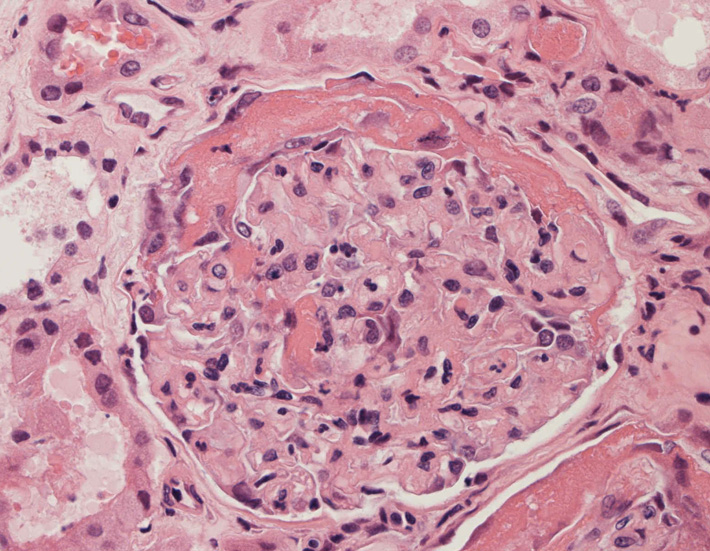

腎臓の病理組織所見-->壊死性糸球体腎炎

Fig.01Fig.02Fig.03

Fig.03(PAS)Fig.04(PAM染色)Fig.05(PAM染色)

Fig.06Fig.07 尿細管壊死